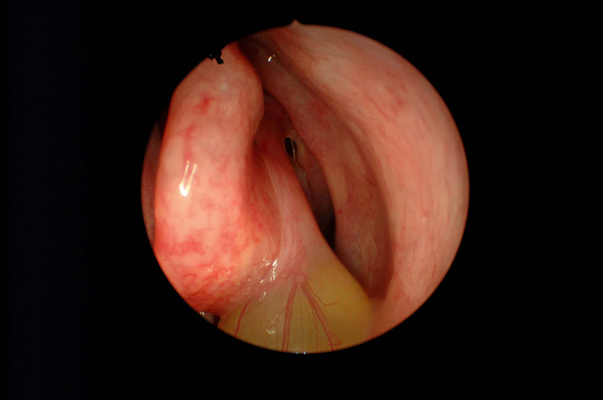

鼻竇炎圖片